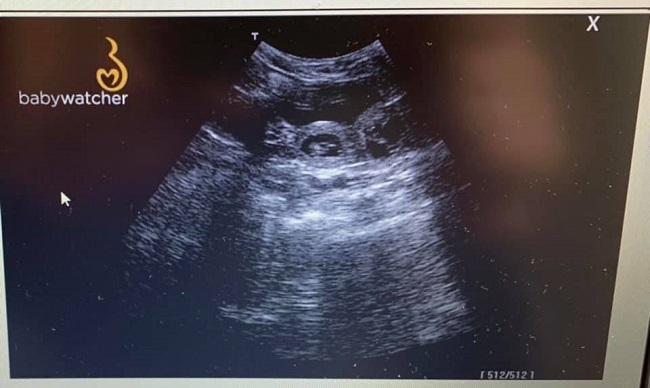

24.02.2021 Ultraschall am 32. Tag der Trächtigkeit

Ein erneuter Ultraschall zuhause, ganz entspannt zeigte zahlreiche kleine Passagiere in Melodies Bauch, dicht an dicht gekuschelt <3